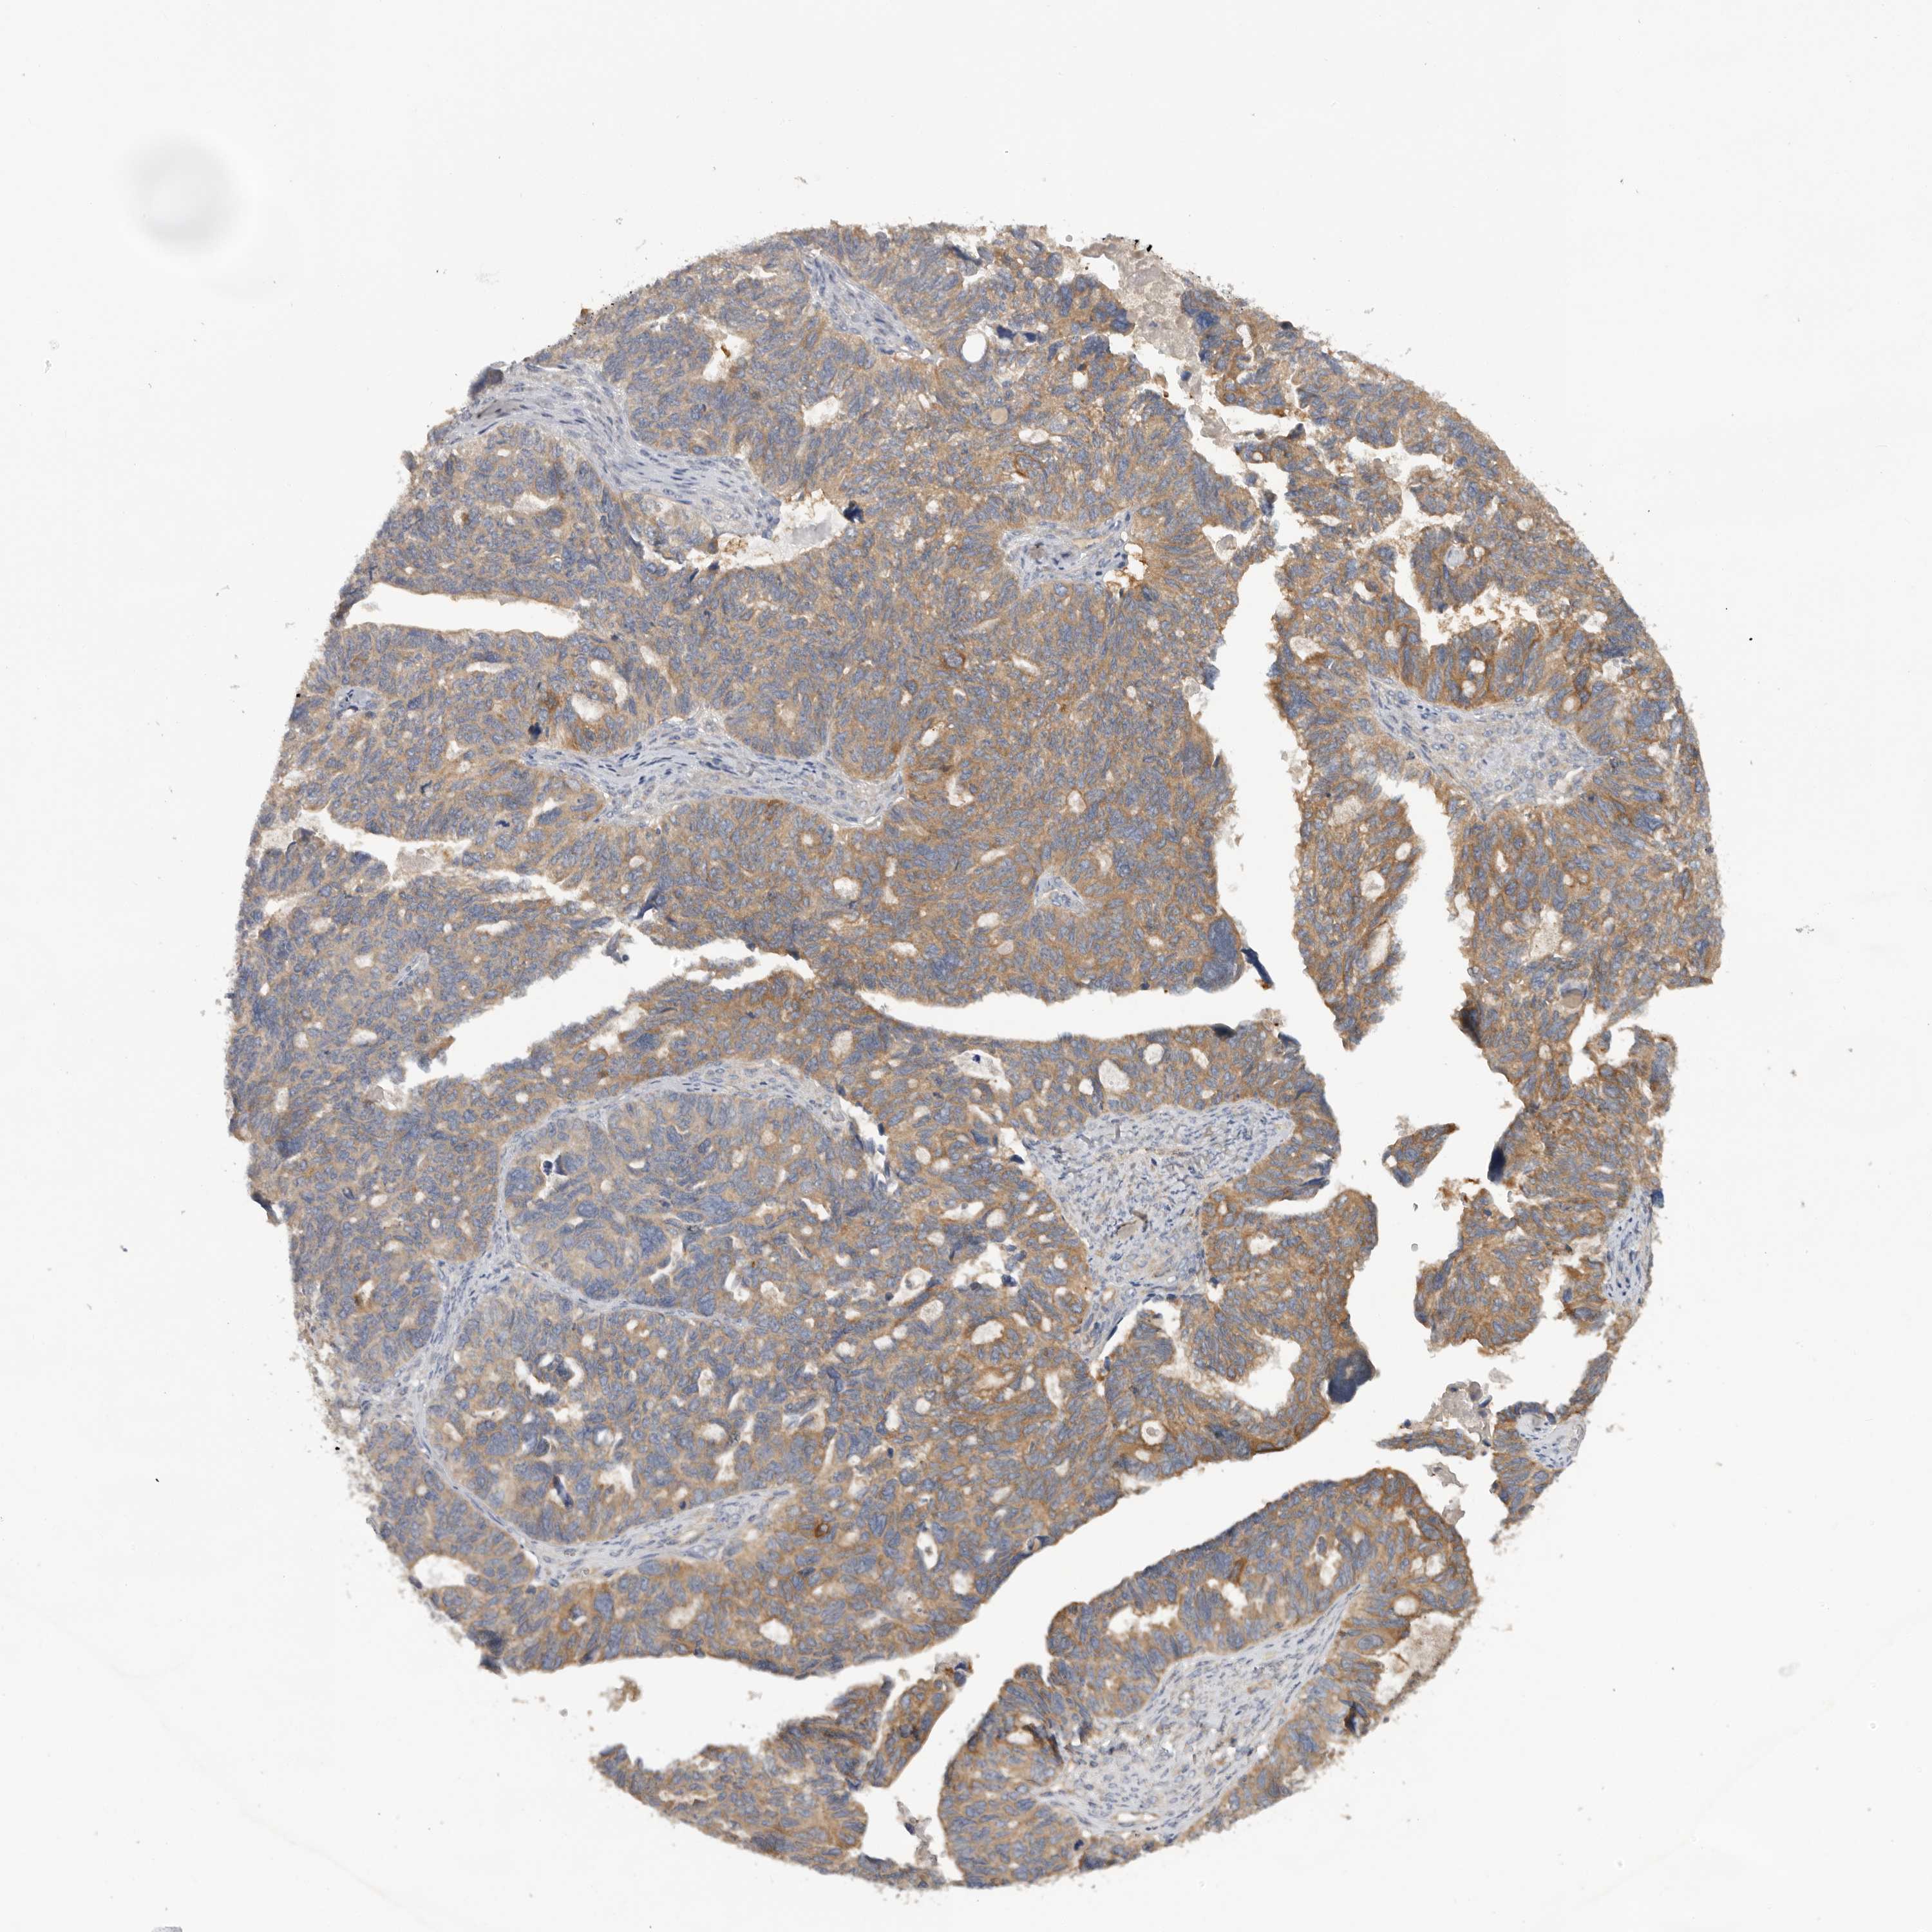

OVARIAN CANCER - Protein expressioni

A mouse-over function shows sample information and annotation data. Click on an image to view it in a full screen mode. Samples can be filtered based on level of antibody staining by selecting one or several of the following categories: high, medium, low and not detected. The assay and annotation is described here.

Note that samples used for immunohistochemistry by the Human Protein Atlas do not correspond to samples in the TCGA dataset.

Antibody stainingi

Antibody staining in the annotated cell types in the current human tissue is reported as not detected, low, medium, or high, based on conventional immunohistochemistry profiling in selected tissues. This score is based on the combination of the staining intensity and fraction of stained cells.

Each image is clickable and will lead to virtual microscopy that enables deeper exploration of all samples and also displays staining intensity scores, fraction scores and subcellular localization as well as patient and tissue information for each sample.

Antibody HPA024313

Antibody HPA027983

Antibody HPA028628

Staining

High

Medium

Low

Not detected

Intensity

Strong

Moderate

Weak

Negative

Quantity

>75%

75%-25%

<25%

None

Location

Nuclear

Cytoplasmic/membranous

Cytoplasmic/membranous,nuclear

Cystadenocarcinoma, serous, NOS